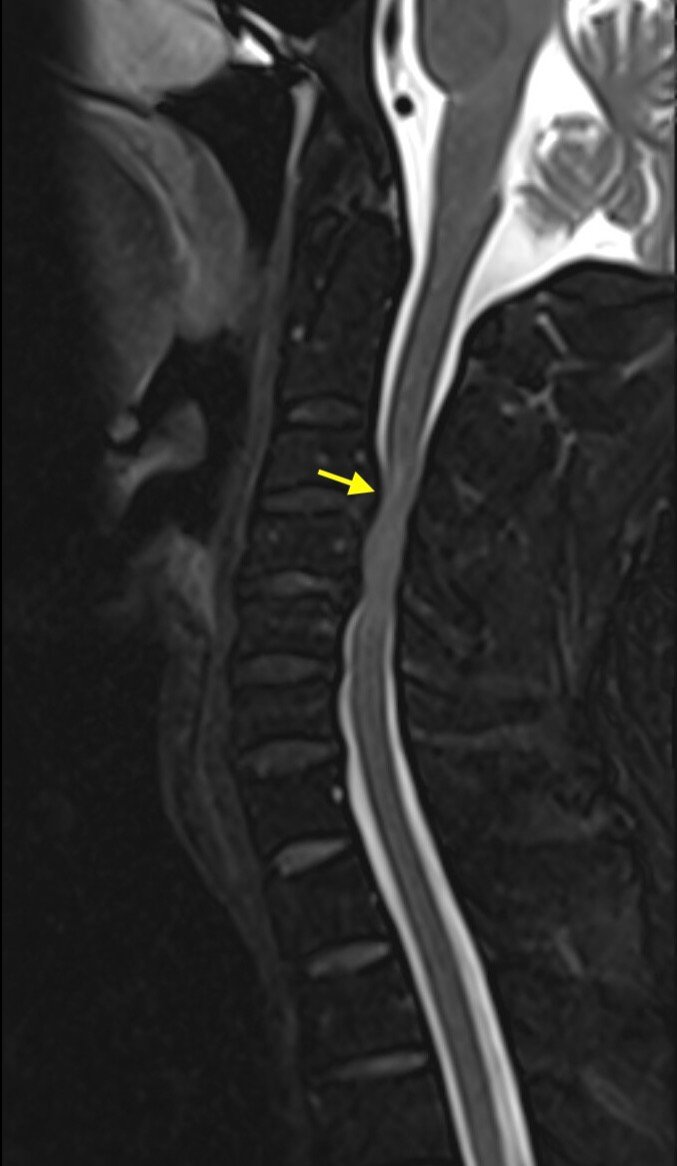

A 44-year-old male presented with sudden onset of severe left arm burning dysesthesia and bilateral leg numbness and weakness for several hours. He denied any recent illnesses or trauma and was previously healthy. His exam showed decreased strength to his left upper extremity, decreased light touch sensation to bilateral lower extremities, and urinary retention. Computed tomography (CT) and magnetic resonance imaging (MRI) of the cervical spine wereperformed, which demonstrated acute cervical myelopathy due to congenital cervical stenosis, a less common finding. Congenital cervical stenosis is the narrowing of the cervical spinal canal that is not due to structural, infectious,vascular, or malignant causes. This is an important diagnosis to consider in patients who present with neurologic symptoms without risk factors for common myelopathy causes (eg, degenerative changes). Early diagnosis and treatment are essential to prevent long term neurologic deficits.